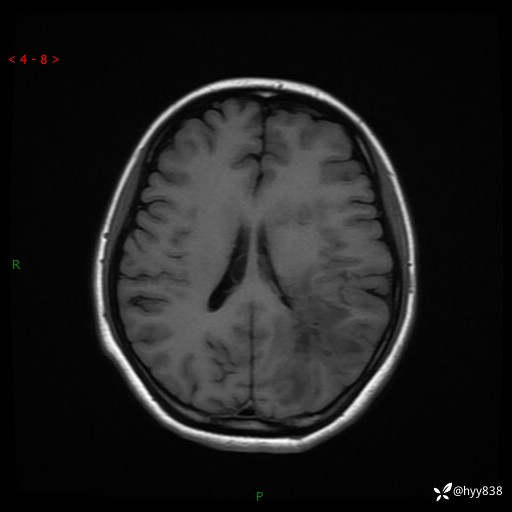

颅脑MRI平扫+增强